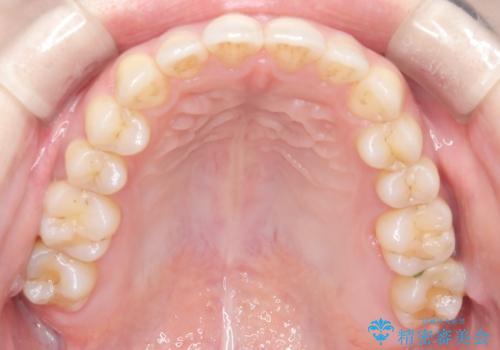

- 笑った時の前歯の見た目が気になることを主訴に来院されました。

上の歯が下の前歯を少し隠すぐらいを目指し、インビザラインにて治療を行いました。

- 1年6ヶ月